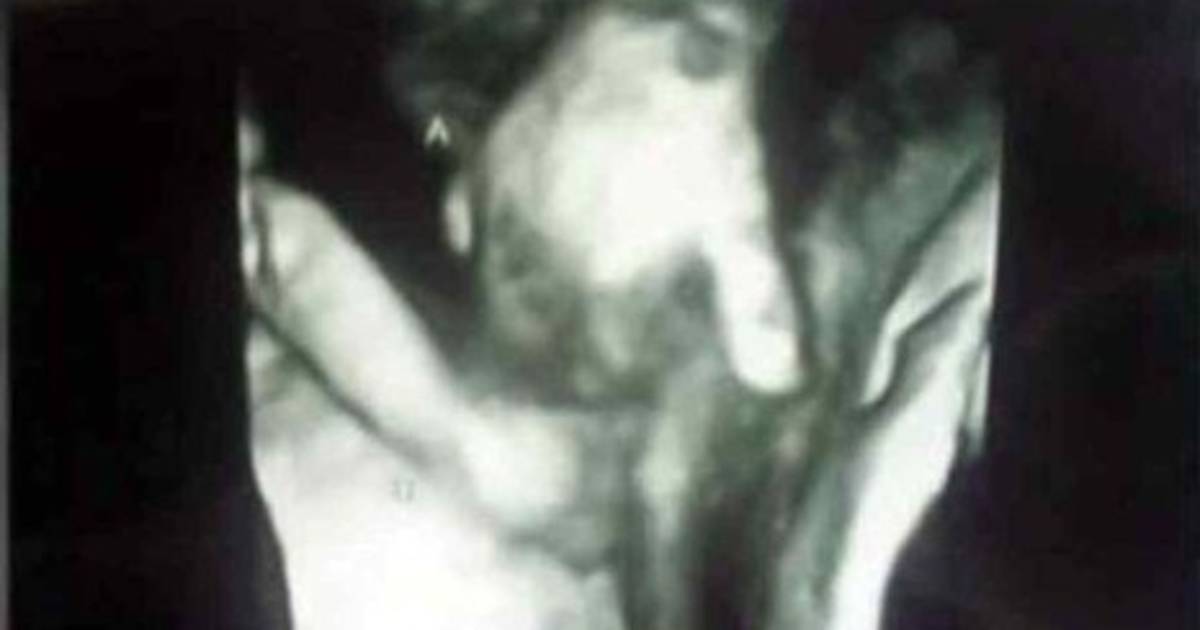

Medios de comunicación en diferentes partes del mundo han compartido la imagen e historia de los hijos de Brittani Mclntire y su marido, gemelos que aparecen tomados de la mano en un ultrasonido.

La foto es realmente conmovedora no solo por el acto de amor entre los hermanos si no porque uno de los bebés tiene probabilidades de no sobrevivir tras su nacimiento, ya que tiene un agujero en el corazón y problemas en con su cerebro.

La madre de las criaturas Mclntire, dijo a la cadena local de noticias ABC6:‘‘Es agradable descubrir lo que se ve en la imagen. Yo los llevo dentro de mi y me gustaría estar con él (su hijo que tiene pocas probabilidades de sobrevivir), pero su hermanita es la única que puede estar ahí, cerca, y nos reconforta saber que si él muere, no estuvo solo en ningún momento’’.

El ultrasonido fue tomado en la sexta semana de embarazo, fue ahí cuando se dio a conocer que el gemelo varón Mason tiene esas complicaciones.